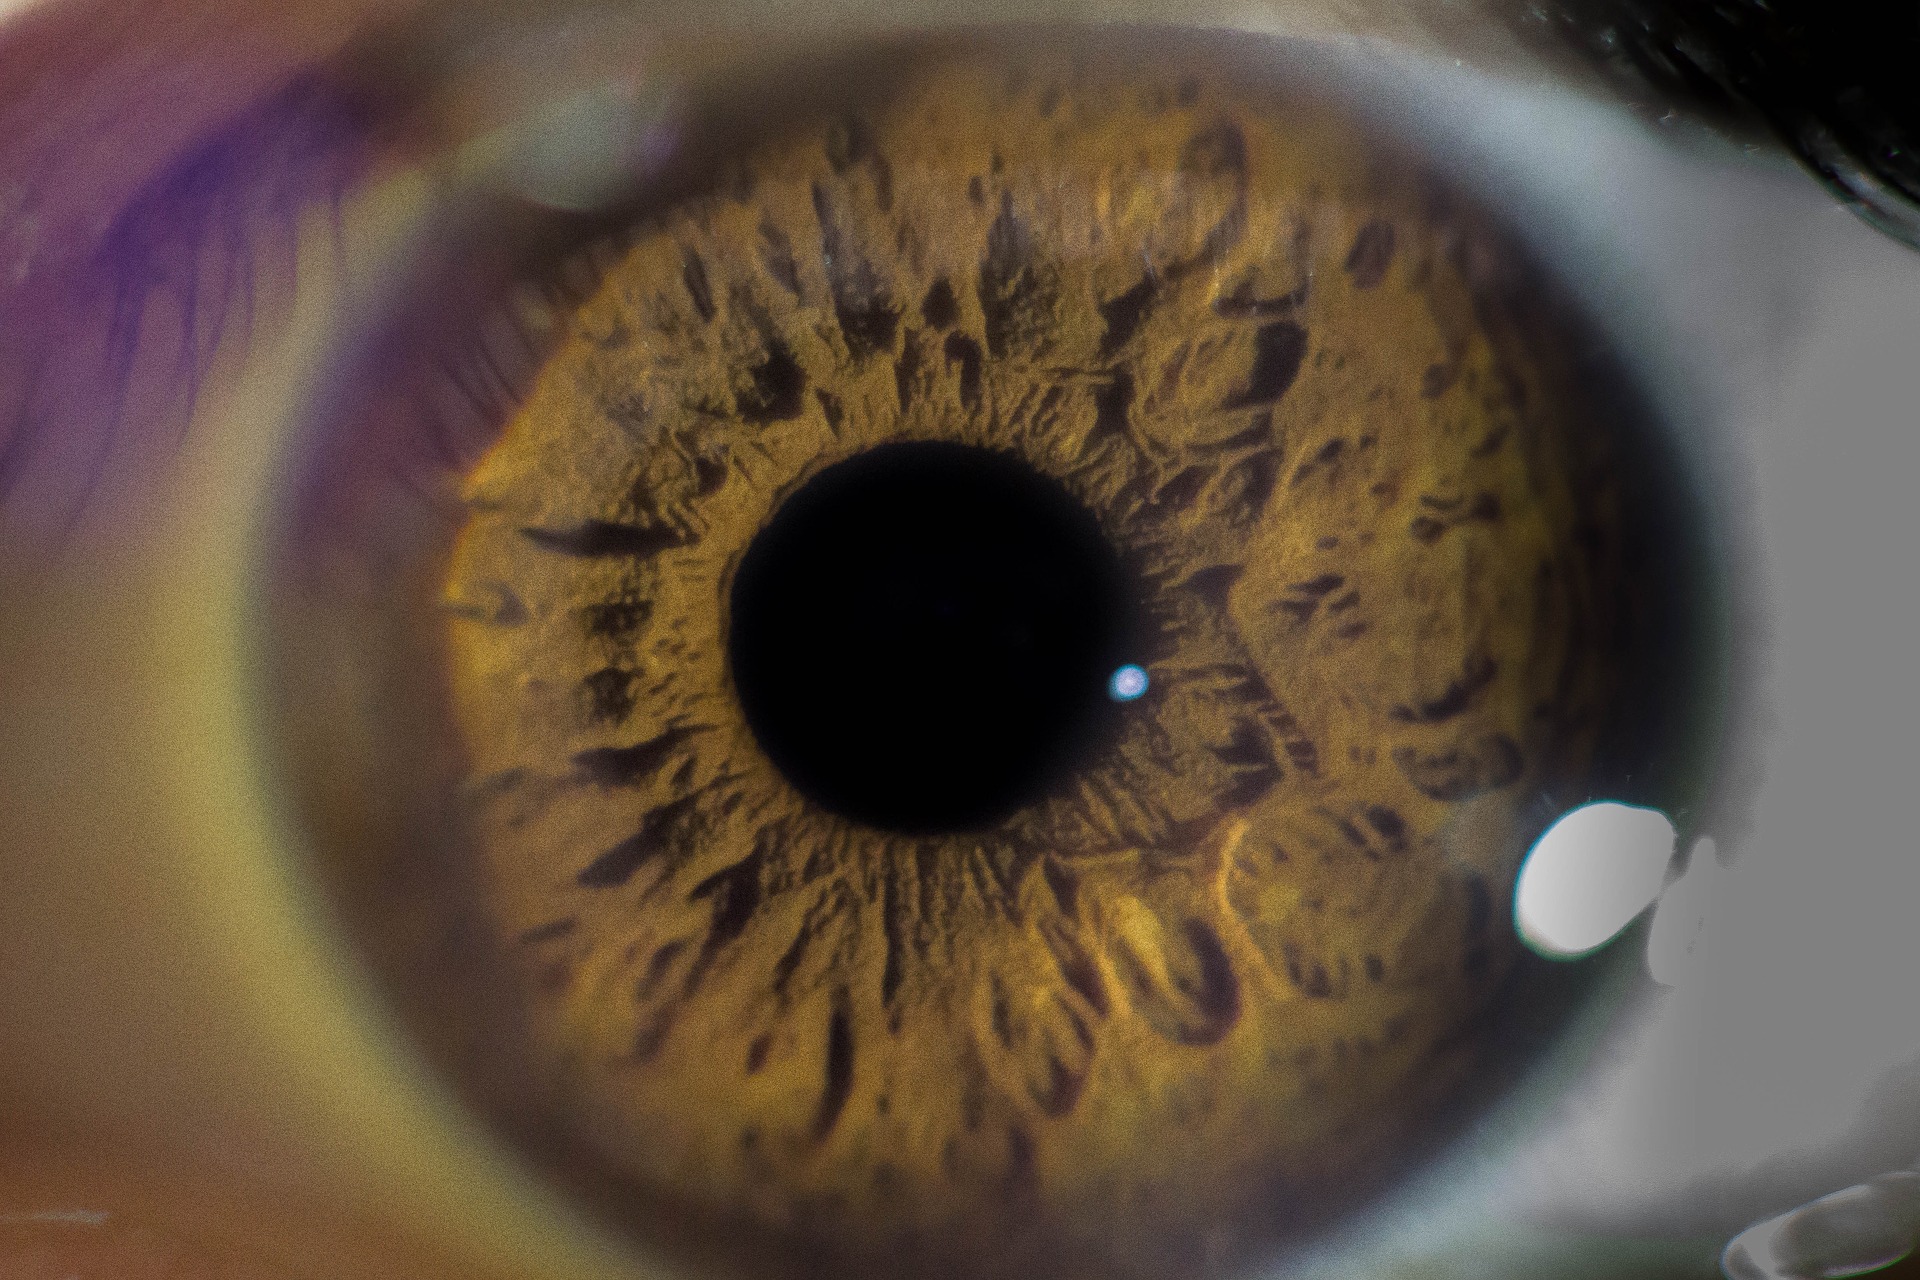

Source : pinterest.com